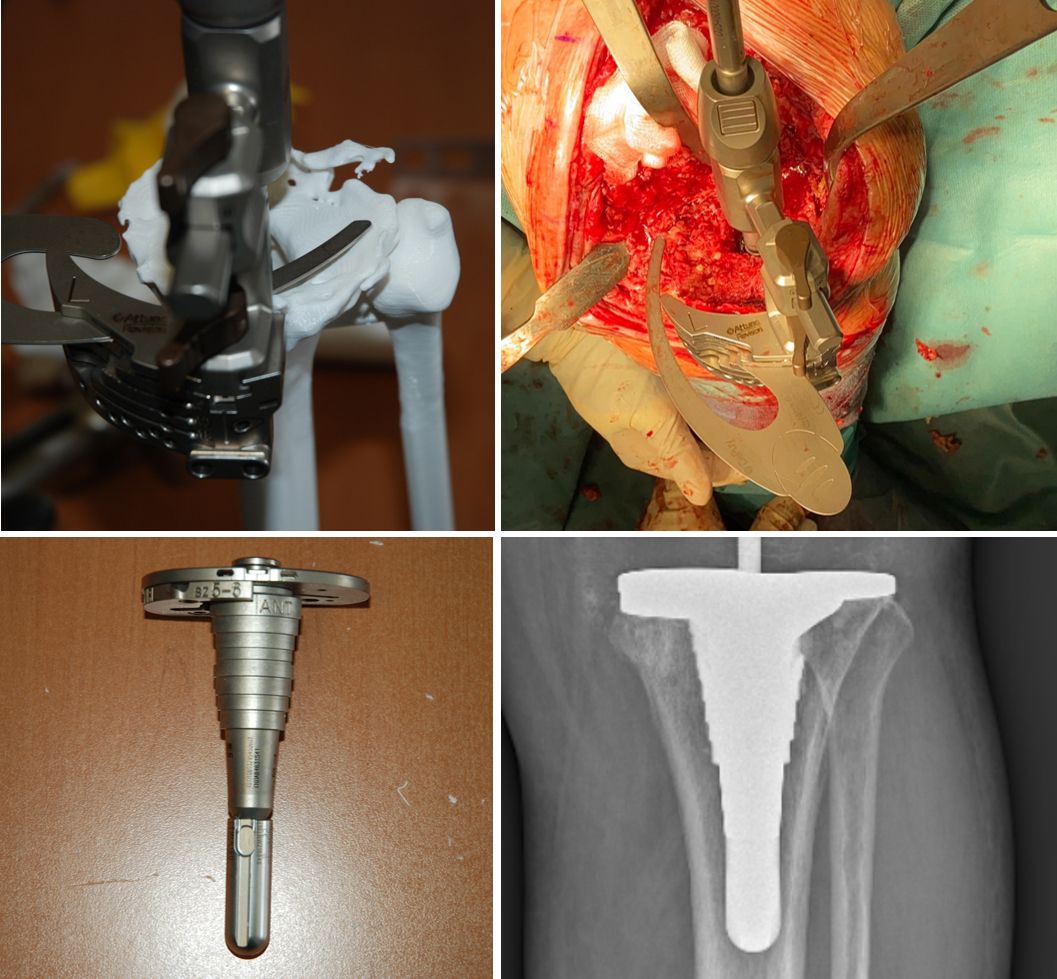

With the HA3D™ model, a complete case report with all relevant measurements is provided. After the validation of the printed project, the model is produced with additive manufacturing technology, in particular FDM (Fused Deposition Modeling) technology. PLA (Polylactic Acid) material is the most commonly used for 3D models (Fig. 6-8).

A few days before surgery, the surgeon and nurse can "implant" the real prosthesis and perform the upcoming procedure (fig. 6-8) using real instrumentation on the newly produced 3D model to determine the size of the components (fig. 9) and the need for wedges or cones, if necessary, to restore the correct position and rotation of the joint axis.

During implantation all the different options for stem length and offset, spacers, blocks and sizes can be preselected and every feature of the implant is already known and can be assembled. In many cases the preop plan fits very well with the final intraoperative solution (fig. 10-12).